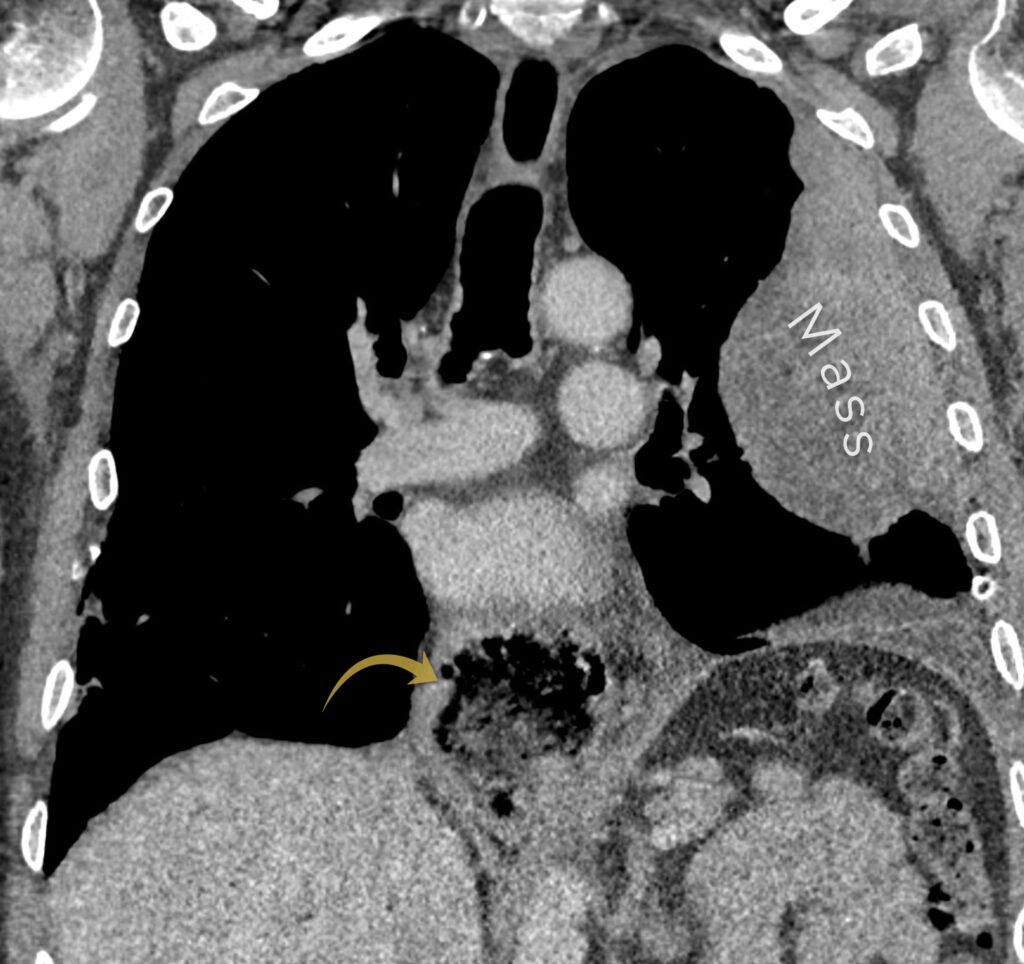

The CT confirms an enhancing mass related to the pleura. Again, the obtuse angle the mass forms with the chest wall tells us the lesion is related to the pleura rather than being a parenchymal lung mass.

Pleural mass confirmed on CT. Also have a look at the gastric pull up (yellow arrow)

CT also shows us something else: the oesophagus has been resected due to oesophageal cancer and the stomach has been pulled up (a ‘gastric pull up’). Having a diagnosis of cancer changes the picture, instead of a primary malignancy of the pleura, ie mesothelioma, we now have to consider metastatic disease of the pleura.

Have a look at the CT scan in more detail below:

In the image below we can see the biopsy needle is placed into the left pleural mass. We can again see the gastric pull up behind the trachea.